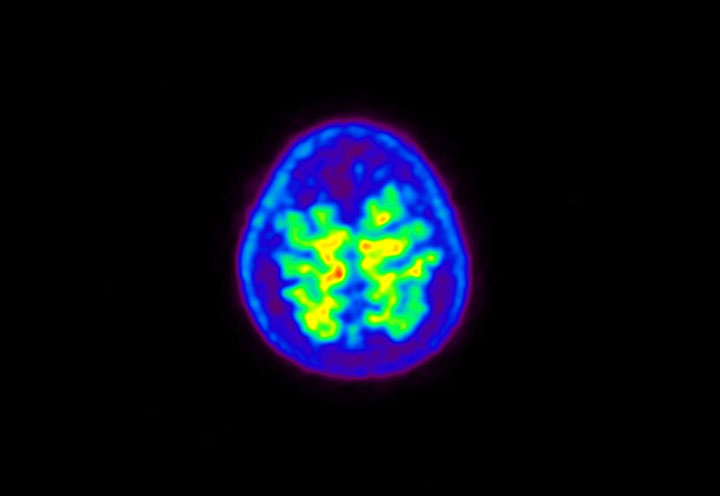

Head / Case5 : Amyloid

Courtesy : Kindai University Hospital

- Imaging protocol

- Injected dose: 4.27 MBq/kg, 18F-Flutemetamol

- Uptake time: 99 minutes

- Scan time: 20 minutes